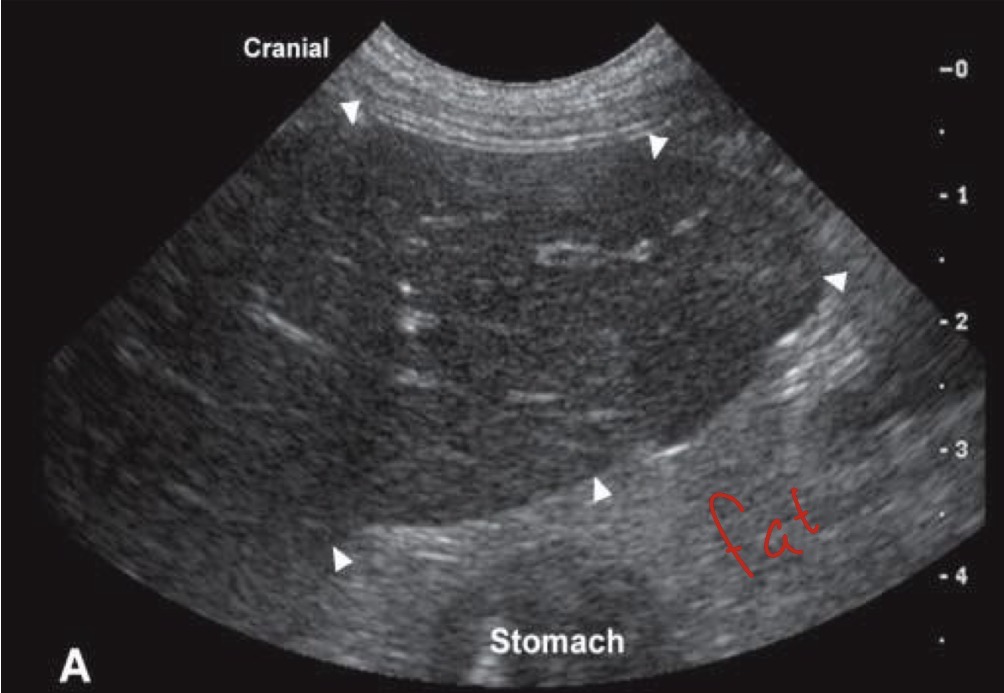

Left liver more hypoechoic

Right spleen more hyper echoic

What organs are labeled here and what is their echogenic pattern?